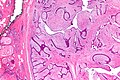

| LM | either (1) or (2): (1) large slit-like spaces, (2) cellular stroma - may be myxoid; +/-infiltrative border, +/-mitoses, +/-nuclear atypia, +/-"stromal overgrowth" ~ stroma fills microscopic field (see microscopic section) |

Microscopic

Features - either 1, 2 or both of the following:

- Large slit-like spaces - key feature. †

- Cellular stroma - key feature. †

- May be myxoid.

- +/-Infiltrative border.

- +/-Mitoses.

- +/-Nuclear atypia.

- +/-"Stromal overgrowth" ~ stroma fills microscopic field (see below).

Notes:

- † Large slit-like spaces are required for a benign phyllodes tumour.

- Slit-like spaces may absent in a borderline phyllodes or a malignant phyllodes.

- A cellular tumour without features suggestive of malignancy and without slit-like spaces is a cellular fibroadenoma.